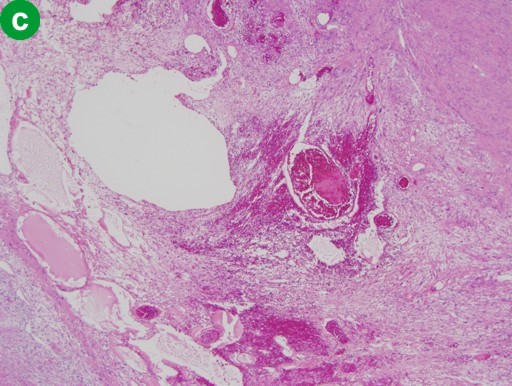

A distal pancreatectomy together with a splenectomy and lymph node dissection were performed. The cut surface of the resected pancreas showed a well-demarcated, pale yellow, solid tumor within the pancreas parenchyma. The tumor was 3x3x3 cm in size, and composed of a mixture of solid areas and myxomatous and/or hemorrhagic areas (Figure 3a). Histopathological examination of the tumor revealed proliferation of the spindle cells showing interlacing and palisading patterns (Figure 3b). Focal hypocellular areas showing edematous and myxomatous degeneration, hemorrhage and hemosiderin deposition, and dilated hyalinized vessels were also noted (Figure 3c). The proliferating cells showed minimal pleomorphic nuclei, but no mitotic figures were found. Immunohistochemically, the spindle cells were positive for S-100 protein and vimentin, and negative for alpha-smooth muscle actin, CD34 and cytokeratin. Based on these findings, the tumor was diagnosed as a pancreatic schwannoma of mixed Antoni A and Antoni B types. No remarkable findings were noted in the spleen and the dissected lymph nodes. At a 24-month follow-up after surgery, the patient is doing well without any recurrent disease.

Figure 3. a. The cut surface of the resected tumor is composed of a mixture of solid areas and myxomatous and/or hemorrhagic areas. b. Histopathology of the resected specimen shows proliferation of the spindle cells in interlacing and palisading patterns (Antoni A) (H&E, original magnification x100). c. Edematous degeneration areas with hemorrhage, hemosiderin deposition and hyalinization of the dilated vascular walls (Antoni B) (H&E, original magnification x100). |

Microscopically, schwannomas generally consist of two alternating components: an organized cellular component consisting of long bipolar cells which often form a palisading arrangement and/or Verocay bodies (Antoni A area) and a loose hypocellular, degenerative component (Antoni B area) [31]. Most of the pancreatic schwannomas reported also had Antoni A and Antoni B areas in various proportions as was the case in the present tumor. The degenerative changes gave rise grossly to a frequent cystic component.